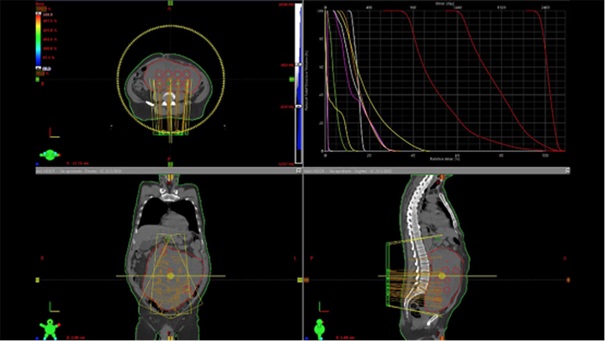

Kỹ thuật xạ trị lập thể phân liều (Spatially Fractionated Radiation Therapy - SFRT) là một kỹ thuật xạ trị cho phép cung cấp liều lượng bức xạ khác nhau theo phân vùng trên một khối u lớn, đồng thời bảo vệ được các cơ quan lành xung quanh [4, 5]. Do tính không đồng nhất trên một khối u nên bằng cách sử dụng mô hình mô phỏng trên máy tính để phân vùng liều lượng. Kỹ thuật này sẽ giúp tăng sự hiệu quả điều trị khối u khi cung cấp đồng thời các liều lượng bức xạ cao và thấp thích hợp trên một khối u. Những tiến bộ công nghệ hiện nay, đặc biệt là với các công cụ mô phỏng chính xác đã hỗ trợ áp dụng kỹ thuật SFRT rất an toàn và hiệu quả.

Hình 3. Xạ trị khối u vùng bụng - chậu bằng kỹ thuật xạ trị lập thể phân liều (SFRT).